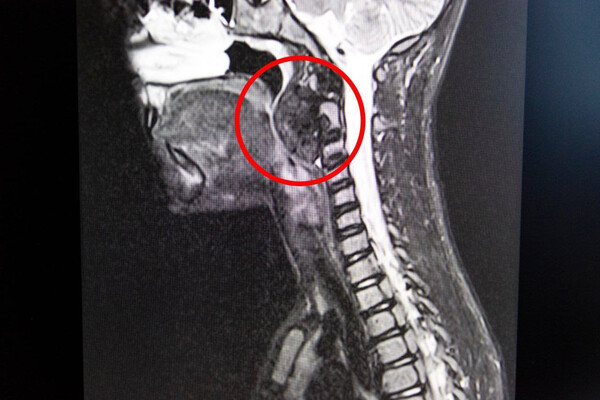

В Кемерове врачи удалили у девятилетнего мальчика опухоль в горле размером с яйцо

Родители маленького пациента рассказали, что ребенок начал задыхаться ночью во сне, испытывал сложности с глотанием во время приема пищи. В ходе обследования медики выявили в заглоточном пространстве гигантскую опухоль размером с куриной яйцо.

Было принято решение о хирургическом вмешательстве. Новообразование мешало пациенту дышать и сдавливало шейные позвонки.